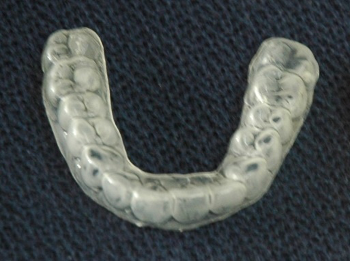

装着する時間はご飯を食べるとき以外はしておいた方がいいですが、特に就寝時、スポーツ、庭仕事をするときなどは必ずして下さい。マウスピースはボクシングの選手がするような分厚いものではありませんので違和感や異物感は少ないです。

費用は保険がききますから3割負担の方で5.000円ぐらいです。睡眠時無呼吸症候群用(医師の紹介状が必要)、いびき用のマウスピースもあります。